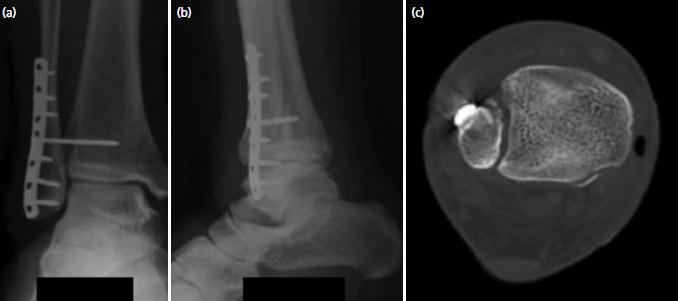

Bosworth fracture dislocations of the ankle are rare injuries of the ankle caused by extreme external rotation of the supinated foot where the proximal fibula fracture fragment is posteriorly dislocated and entrapped behind the posterior-lateral ridge of the tibia. This case series aims to document three such cases treated in our institution over a nine year period. We also provide a review of 129 cases in the existing literature.

Closed reduction was unsuccessful in all three patients, and all required open reduction. One patient had an uncomplicated recovery whilst the remaining two suffered significant soft tissue complications. One patient suffered severe soft tissue swelling preventing primary closure at the time of surgery, whilst another suffered post-operative wound dehiscence and infection. Eventually all fractures healed, and all three patients obtained satisfactory AOFAS scores.

The diagnosis of Bosworth fracture dislocations of the ankle is often delayed or missed, due to its rare occurrence. Closed reduction is often unsuccessful, and early open reduction is required to avoid poor clinical outcomes due to severe soft tissue damage or even compartment syndrome.